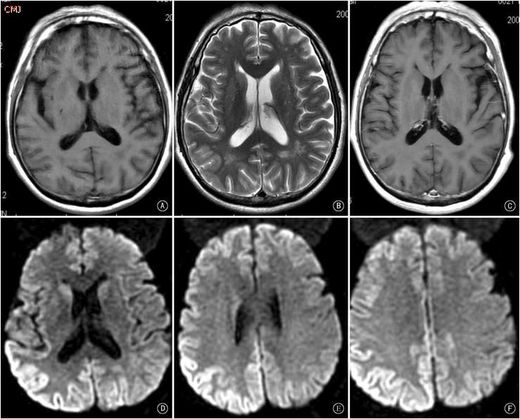

並開始入侵腦部組織,你的腦袋在X光的照片下會變成一個洞一個洞,就如同被散彈槍打過一樣,

這張大腦圖,由右至左可以看到 Creutzfeldt–Jakob disease 的病患腦部逐漸成海綿狀。